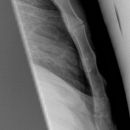

Thorax seitlich

Darstellung der Sagittalebene des Thorax und der Brustorgane, anliegende Seite richtet sich nach dem Befund, ohne spezielle Angabe wird generell links anliegend geröntgt. Atemphase: maximale Inspiration.

Wirbelsäule rein seitlich, Sternum seitlich getroffen, komplette Darstellung der Lunge von Lungenspitze bis einschließlich Rippen-Zwerchfell-Winkel. Die Mediastinalstrukturen und retrocardialen Gefäßabschnitte sind gut differenzierbar und der Herzhinterrand scharf abgrenzbar.